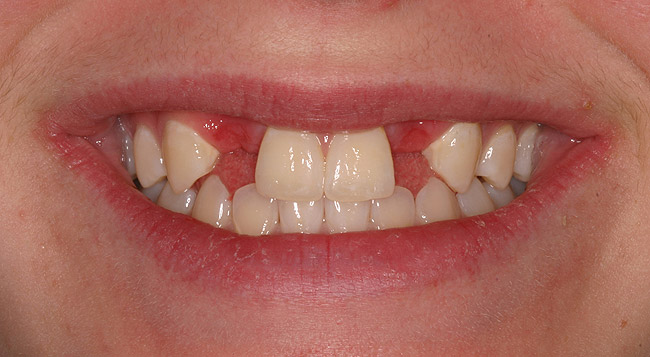

Figure 4a  Before treatment, missing lateral incisors replaced with failing conventional cantilever FPDs with canine abutments. Patient lacked inter-root space for implant therapy, denied orthodontic therapy, and chose revision FPD therapy.

Figure 4a

Figure 4b  Before treatment, missing lateral incisors replaced with failing conventional cantilever FPDs with canine abutments. Patient lacked inter-root space for implant therapy, denied orthodontic therapy, and chose revision FPD therapy.

Figure 4b

Figure 4c  Completed revised 2-unit porcelain-fused-to-gold cantilever FPDs, ovate pontic design, cemented with Maxcem Elite‚Ñ¢ (Kerr Corporation).

Figure 4c

Figure 4d  Completed revised 2-unit porcelain-fused-to-gold cantilever FPDs, ovate pontic design, cemented with Maxcem Elite‚Ñ¢ (Kerr Corporation)..

Figure 4d